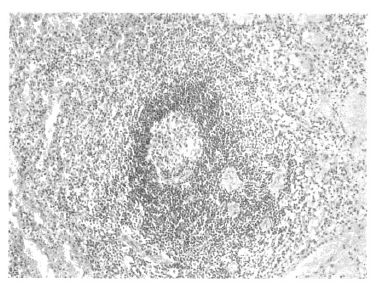

A 37-year-old woman was admitted to our hospital due to gum bleeding and petechiae in both lower extremities for three days. She had a known diagnosis of AITP and had undergone a splenectomy 11 years ago. She denied taking any medications prior to this hospitalization. On admission, her temperature was 36.6°C and her blood pressure was 110/70 mmHg. The physical examination was unremarkable except for the oozing of blood in oral cavity and a diffuse petechiae in both lower extremities. A splenectomy scar was present in her abdomen. The WBC was 7,200/mm3, hemoglobin was 12.4 g/dL, and platelet count was 3,000/mm3. The serum electrolytes and liver chemistry were within normal limits. Serum urea nitrogen and creatinine were normal. A routine urine analysis showed the presence of microscopic hematuria. The coagulation profile was all within the normal limits. Daily prednisolone and intravenous immunoglobulin (IVIG) were started. A spleen scan obtained after the intravenous injection of technetium-99m-labeled denatured RBC revealed a focal uptake in the posterior aspect of the left upper quadrant, and these findings are consistent with the presence of an accessory spleen (Figure 1). A computed tomographic (CT) scan of the abdomen revealed a 2×2 cm sized soft tissue lesion on the left sub-diaphragmatic area (Figure 2). On the 22nd hospital day, an accessory splenectomy was performed and the operation proceeded without complication. A dark brown mass was obtained and the pathologic finding was splenic tissue (Figure 3). The postoperatively platelet count soon increased to 71,000/mm3 and the patient was discharged. Two months after the accessory splenectomy, her platelet count dropped to 5,000/mm3. A repeated follow-up spleen scan did not show any remaining accessory spleen. A bone marrow examination showed there was still adequate megakaryocytes with normal hematopoiesis (Figure 4). She is being managed with oral cyclophosphamide with a stable platelet count in the range of 50000/mm3 at present.